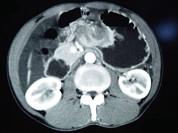

问题 男,65岁,中上腹痛腹胀、消瘦、乏力、纳差,影像检查如图,最可能的诊断是()

选项 A.胃间质瘤 B.萎缩性胃炎 C.肥厚性胃炎 D.胃窦癌 E.胃淋巴瘤

答案 D